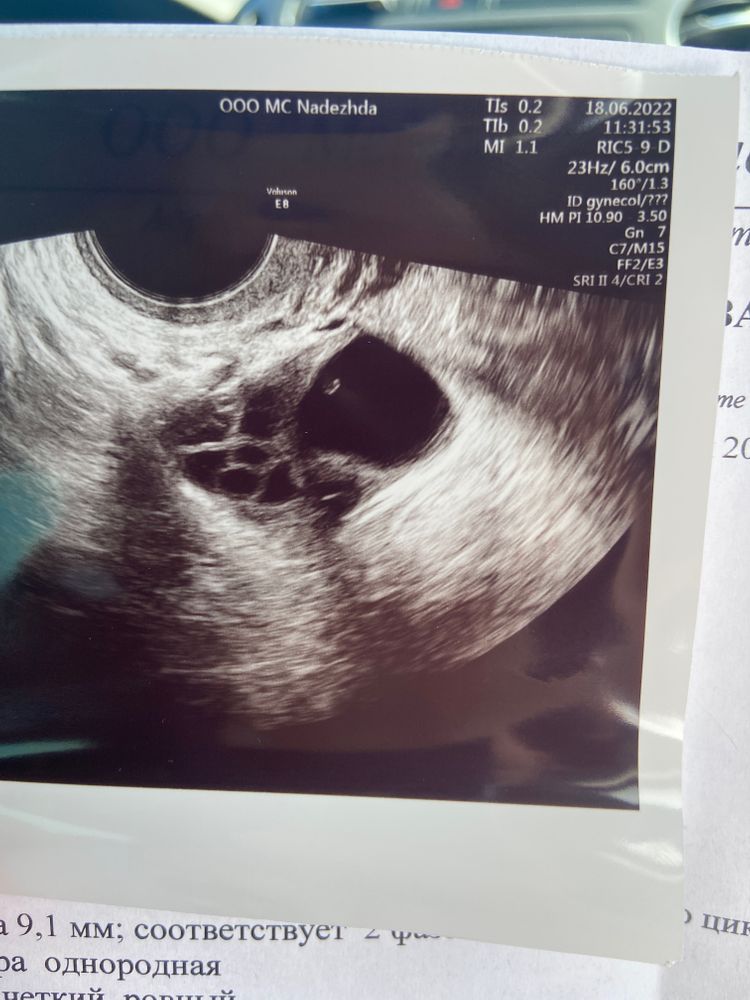

Что это?фото узи прилагаю. Я такое первый раз вижу

Узист говорит, что доминантный фолликул лопнул и образовалась киста жёлтого тела. У меня подсадка через 3 дня. Повлияет ли как то на протокол